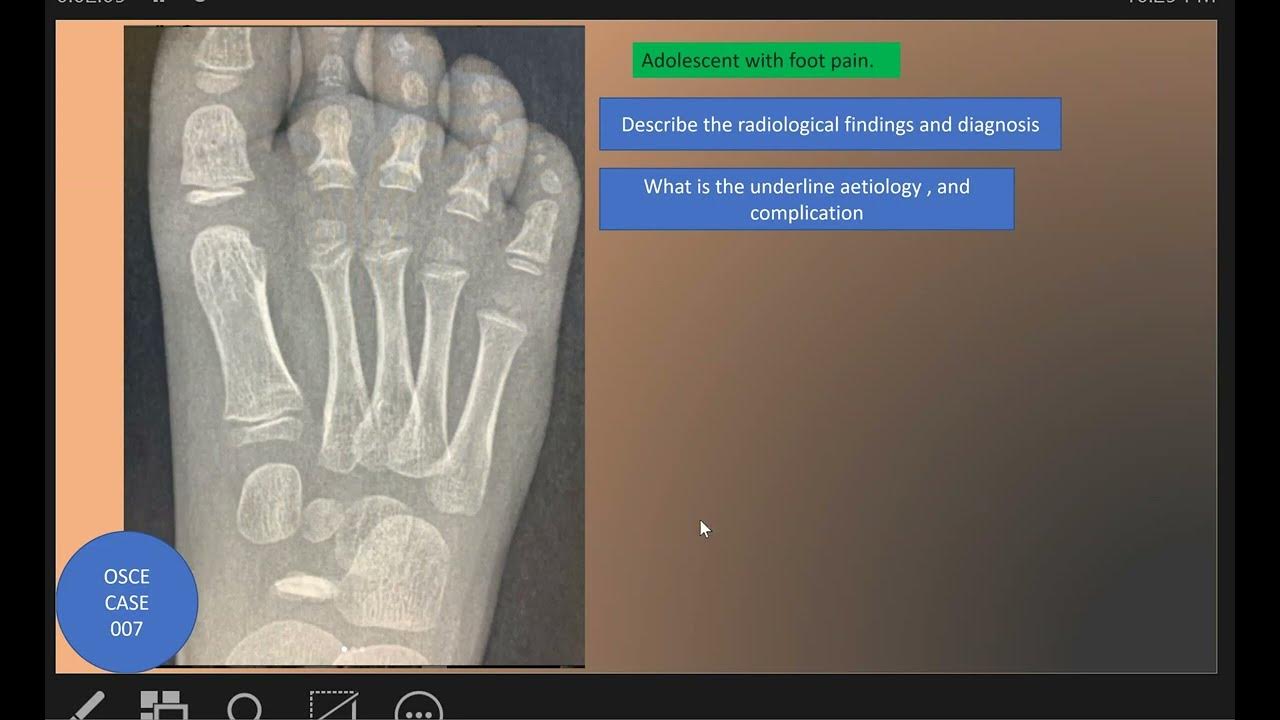

From www.youtube.com

OSCE Case 007 Kohler Disease YouTube Kohler's Disease Causes Avascular necrosis is also sometimes incorporated. Web kohler’s disease is a rare condition that causes the bones in the arch of the foot to become inflamed. Web köhler disease, first described by alban köhler in 1908, is a rare bone disorder of the foot that occurs in children,. Web kohler's disease is a rare idiopathic condition caused by avascular necrosis. Kohler's Disease Causes.